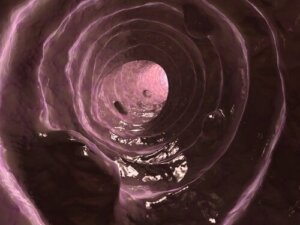

Slem är ett ämne som utsöndras av tarmslemhinnan – liknande det som produceras av luftvägarnas epitel – och vars funktion är att hålla tjocktarmens slemhinna smörjd och fuktig.

Som du kan se kännetecknas en normal avföring inte bara av att den täcks av en mycket tydlig slemhinna. Det är naturligt att de är något smörjda, men aldrig överdrivet mycket. Kontakta din veterinär om du märker någon form av obalans i din hunds avföring.